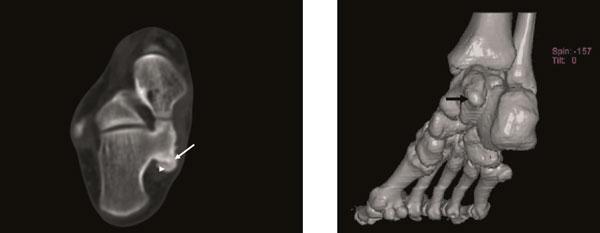

We report the clinical and radiologic findings of a calcaneal osteochondroma with an extremely rare placement and painfull, rapid reccurence following surgical excision in a skeletally mature female. The lesion showed growth the first-operation later and was re-operated. Histopathological examination did not show malignancy.

我们报告了一名骨骼成熟女性跟骨骨软骨瘤的临床和影像学表现,该肿瘤位置极其罕见,手术切除后疼痛且迅速复发。病变在首次手术后出现生长并再次接受手术。组织病理学检查未显示恶性。